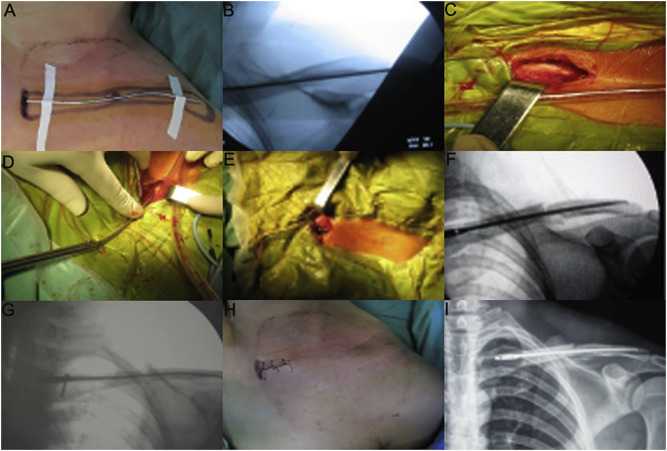

All the patients were positioned on a radiolucent operating table and performed by general anesthesia. Preoperatively, preliminarily closed reduction was processed. Then the inner end and outer end of the clavicle were marked outside the skin with Kirschner wire (Fig. 2 A). After confirming that the outer end of Kirschner wire was located at 1.5 cm from the inner part of the clavicular outer end and its long axis was overlapped with the clavicle using C-arm fluoroscopy device. The duration of fluoroscopy use was chosen based on the insert and fixed time of each patient. In addition, pre and postoperative measurements of the clavicle dimensions were taken by the experiment patients under C-arm fluoroscopy device. The initial length of TEN was determined by the length of remained Kirschner wire (Fig. 2 B). A conical cutter was applied for opening aperture of anterior cortex of the clavicle inner part, and the incision was expanded by our self-designed diamond-shaped medullary cavity file (Fig. 2 C). Afterward, the TEN with predicted length was inserted by a holding device, which was advanced gradually under fluoroscopic control (Fig. 2 D and E). If it was too hard to finish the closed reduction, a transverse small incision was made at the fracture site to assist reduction. In this situation, the periosteum of the fracture end was not stripped, and larger free bone fragment could be bundled up to the fracture end using double 7th silk suture (Johnson Inc., New Brunswick, NJ, USA). During operation, the reduction of fracture and the location of TEN were examined by C-arm fluoroscopy device which patients were positioned on it (Fig. 2 F). If the tail of TEN was slightly longer, the tail part could be tapped gently using homemade stick to assure it parallel to the cortex of clavicle inner end. Finally, the TEN was locked with screw and the small incision was sewed up (Fig. 2 G and H). X-ray radiography below the shoulder with clavicular fractures was routinely used to examine the reduction of fracture and the location of TEN (Fig. 2 I). In all the operations, surgeons were with at least 10 years' experience. Moreover, similar treatment and nursing methods before and after the operation were used to the patients.

Fig. 2

Fig. 2.

Surgical procedures of intramedullary nailing using our self-designed TEN. (A) external location with Kirschner wire; (B) the length of TEN measured under the fluoroscopic control of C-arm machine; (C) the medullary cavity opening with a small size incision in the inner end of clavicle; (D) the insertion of TEN from the inner end of clavicle; (E) the outlook after TEN is completely inserted into the medullary cavity; (F) a good position of TEN is seen using C-arm machine; (G) locking the screw at the tail part of TEN; (H) the postoperative outlook of small size incision; (I) a radiograph obtained just after surgery shows a good position of TEN and satisfactory reduction of fracture.